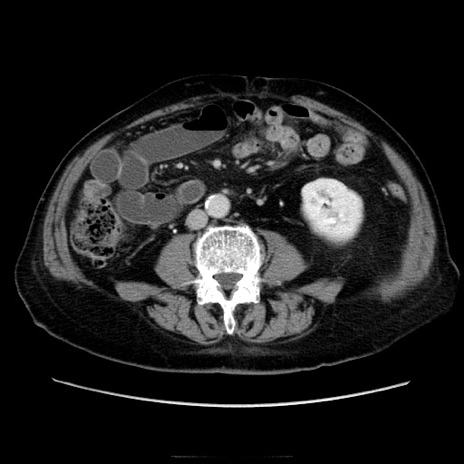

冠状断像

【症例】70歳代男性

【主訴】腹痛

【現病歴】肝硬変・肝細胞癌にてかかりつけの方。約9時間前に食後より腹痛出現。症状が徐々に増悪し、嘔吐出現したため来院。

【既往歴】肝硬変、肝細胞癌(RFA、TACE後)

【身体所見】意識清明、表情苦悶様、BT 36℃、BP 129/78mmHg、P 88bpm、SpO2 97%(RA)、右上腹部から心窩部にかけて圧痛あり、反跳痛なし、筋性防御あり。

【データ】WBC 5800、CRP 0.16